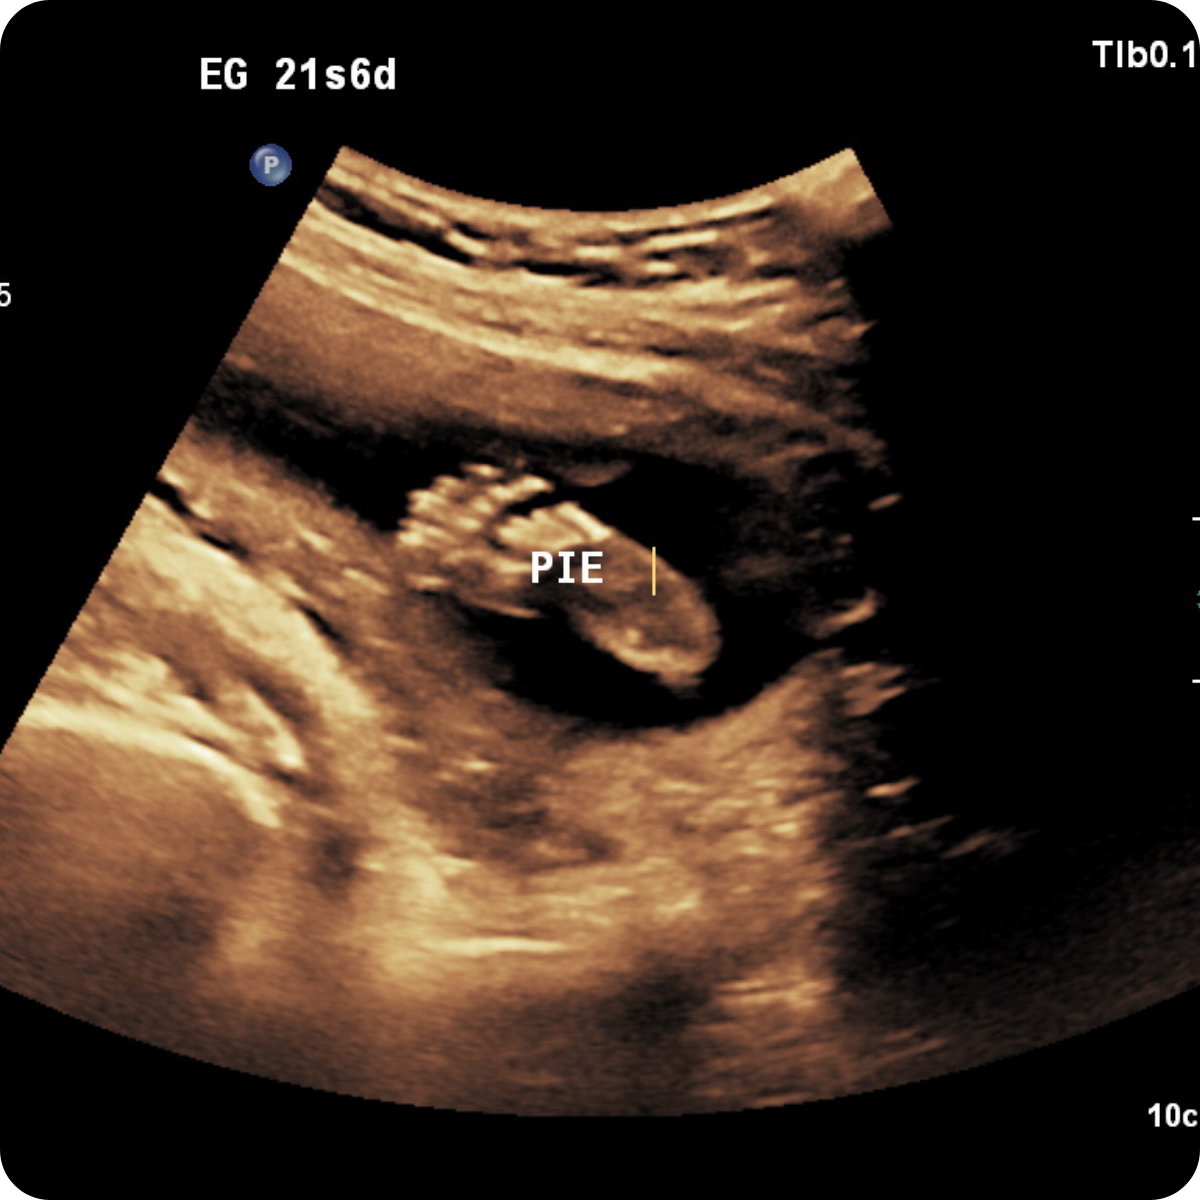

Realizarlo ideal entre las 20 a 24 semanas.

Una de las ecografías más importantes del embarazo. Este es el momento para descartar anomalías fetales de órganos, sistemas y evaluar la circulación placentaria.